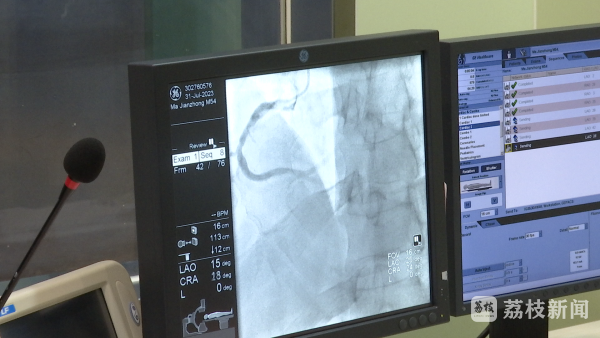

东南大学附属中大医院心血管内科副主任医师李洋说:“这两天也收治了三例急性心梗患者,其中一位60多岁的男性,在家突发意识丧失,到我们急诊室诊断为一个急性的前壁心梗,及时治疗后,患者生命得到了成功地挽救。”

李洋说:“心梗最主要的症状,心前区胸痛、胸闷持续不能缓解,一般是20分钟以上,此外也有其它一些少见的表现,比如意识丧失、晕厥,不能都认为它是中暑,要引起警惕。”